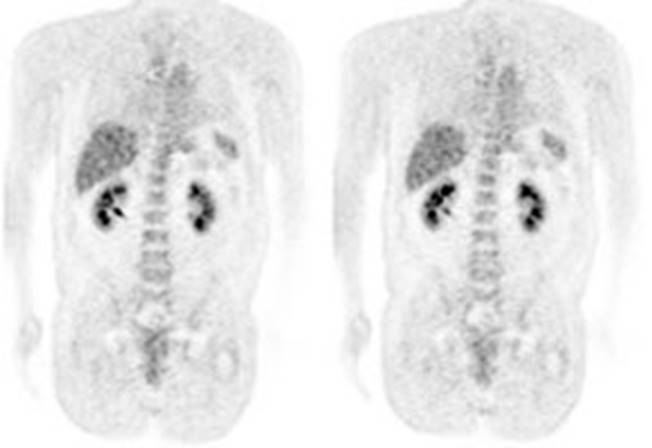

Figure 5 - Genitourinary activity: The image below demonstrates normal

renal and hepatic activity.